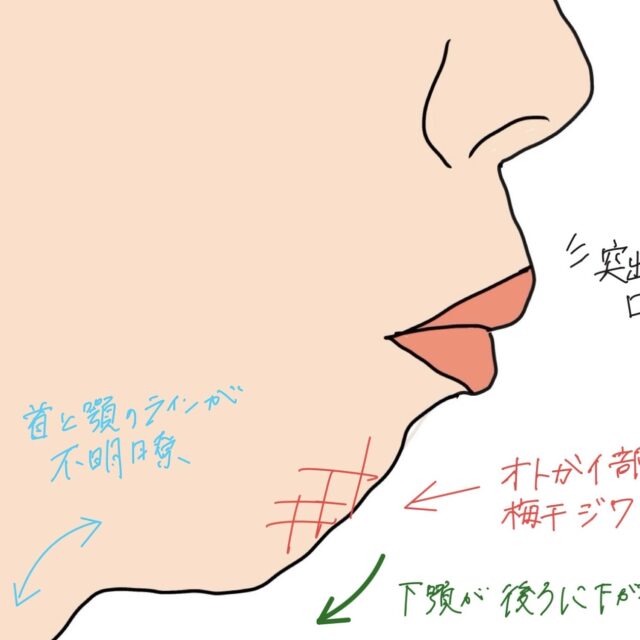

今回の症例で起きている変化ポイント

写真を見ていただくと、

前歯の傾きが内側に入る

- 骨ごと歯が引っ込んでいる→口元も変化しています

- 噛み合わせのズレが改善方向へ→1本対1本で嚙んでいたのが1本対2本のかみ合わせへ